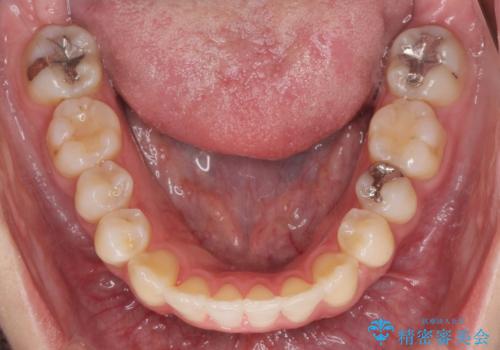

引っ込んだ前歯を並べたい マウスピースと部分ワイヤーのコンビネーション矯正

- 引っ込んで生えてしまっている前歯を並べたい、と矯正治療を希望され来院されました。

まずマウスピース矯正インビザラインシステムで、引っ込んだ歯が並ぶためのスペースを作ったのち、部分ワイヤー矯正を行い短期間での配列を計画します。

このように前歯の部分ワイヤーは引っ込んでしまった前歯や がたつきを素早く改善することができます。